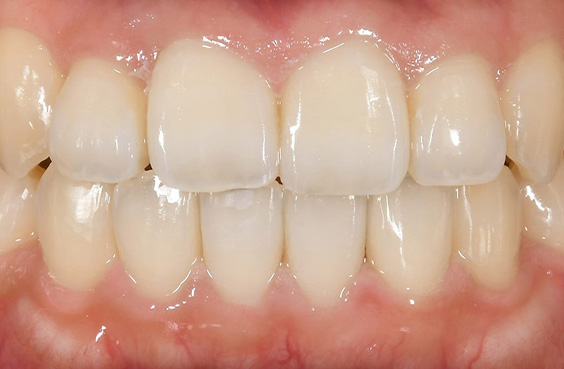

- 症例1

費用 396,000円(税込)

治療期間 6ヶ月

治療内容 マウスピースを用いた歯列矯正

追加処置 IPR

※保険適用外の自由診療となります。

※効果や感じ方には個人差があります。

※マウスピース矯正の主なリスク:

虫歯・歯周病・ブラックトライアングル・歯根吸収・歯肉退縮・1日20時間以上のマウスピース装着が必須・マウスピースにより痛みを感じる可能性・治療中に一時的にかみ合わせに不具合をきたす可能性・リテーナーを最低1年間は1日20時間以上装着、その後徐々に着用時間を減らし、2年目以降は夜間のみの着用推奨。